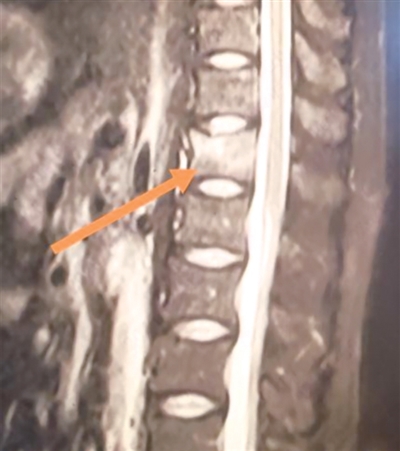

箭头指向为李先生的患处

拿到核磁报告的那一刻,李先生彻底傻眼:胸12椎体压缩性骨折。